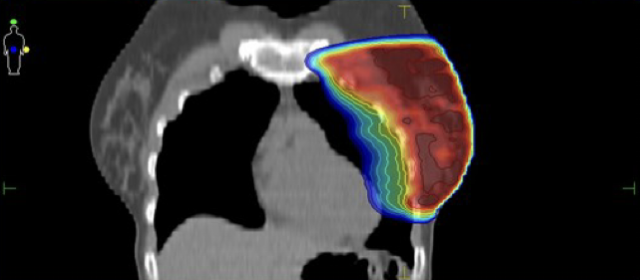

Κατανομή δόσης με την τεχνική ABC

Ελαχιστοποίηση δόσης στην καρδιά και τον πνεύμονα